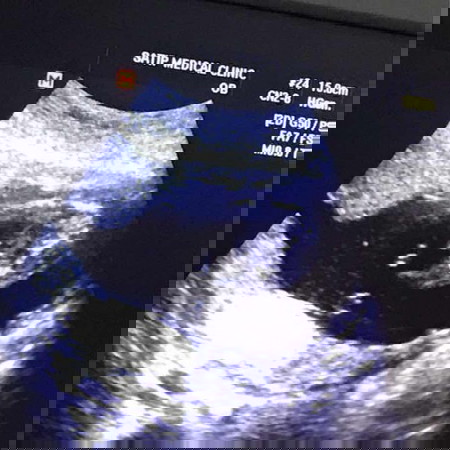

แม่ๆๆว่าผู้หญิงหรือผู้ชายคะ แม่บ้านนี้มองใม่รุ้เรื่องเลยคะ555 Baby 18 weeks #ทีมตุลาคม